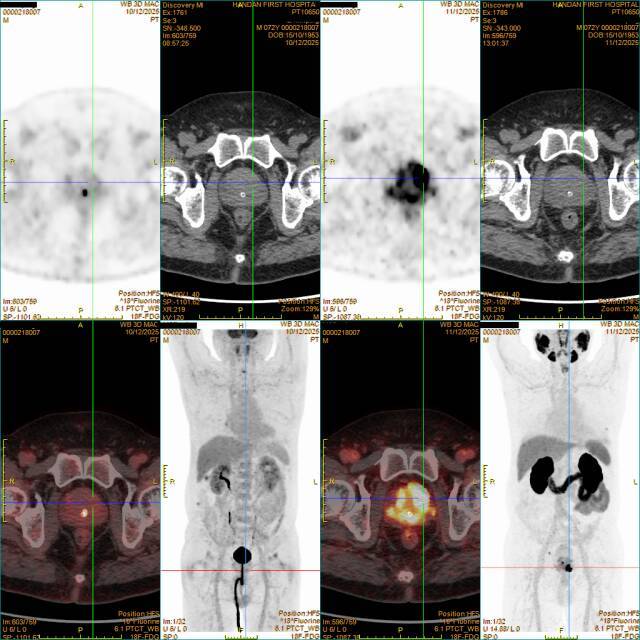

(左四 右四)

72岁的李先生因尿频、排尿不畅半年就诊。18F-FDG PET/CT(左4图)对前列腺内的病灶“视而不见”,而18F-PSMA PET/CT(右4图)却精准锁定了前列腺内原发肿瘤。“多亏了这项精准的检查技术,让我少走了弯路,真的太感谢市一院的医生了!”张先生握着主治医生的手,感激地说道。